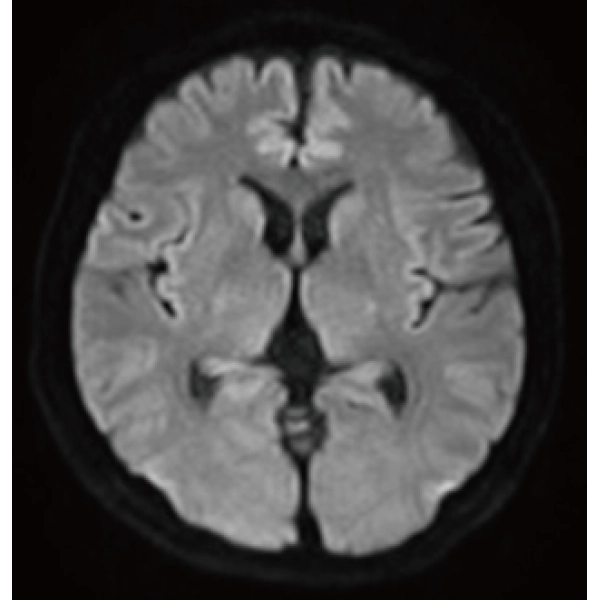

"DLR" is applicable to all body parts and promotes high speed imaging and diagnostic efficiency

IP-RAPID x DLR Plus can also shorten imaging time, allowing more images to be taken in the same examination time.

Additional imaging, such as different image types and cross sections, can be added to the conventional examination to increase the amount of information and make the diagnosis more reliable.

Deep Learning technology*8 enables image quality adjustment after imaging is complete. It optimize SNR and improve image sharpness by processing MRI signals in stages (k-space signal processing). This brings super-resolution and reduces truncation artifacts.